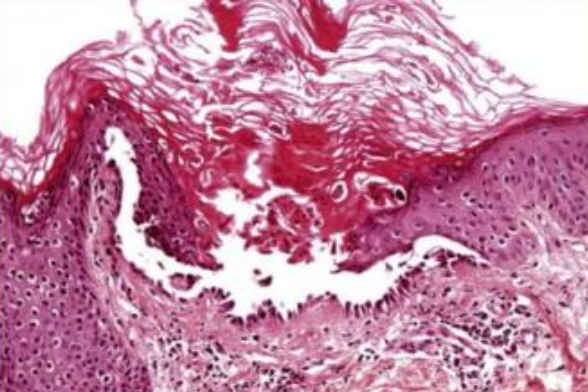

White Sponge Nevus

(Cannon disease)

體顯性 兩側的頰黏膜,出生時、孩童早期

• 口腔黏膜的正常角質化缺陷

• 對稱

• keratin 4 和 keratin 13 表現在上皮的棘狀上皮細胞層

• hyperparakeratosis, acanthosis

• spinous layer 清澈的細胞質

• 表層細胞核周圍嗜酸